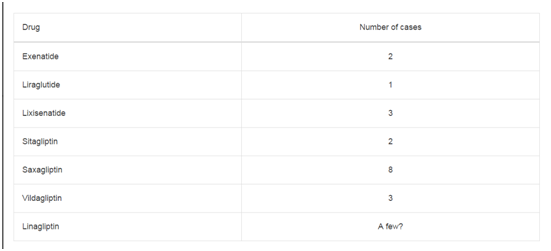

Table 1

Table 1

Clinical and pathological characteristics of patients, results of 18F-FDG PET/CTand contrast enhancement CT.

Abbrevations: AC: Adenocarcinoma; MAC: Mucinous Adenocarcinoma; SRCC: Signet Ring Cell Carcinoma; PDCH: Poorly Differentiated Cohesive Carcinoma;

M: Male, FM: Female; GL: Gastric Lesion; LNM: Lymph Node Metastases; DM: Distant Metastases; CECT: Contrast Enhancement CT; *: Total Number Of Disease

Involved Areas Proved By Gold Standard; -: Not Evaluated in Terms of Gold Standard; not available: Patients with Only Thoraks CT

Results

In 14 patients 18F-FDG PET/CT was performed for restaging and

in 6 for staging. Ten patients underwent both thorax and abdomen

contrast enhancement CT and 18F-FDG PET/CT and in remaining 10,

only one regional contrast enhancement CT was present. The mean

time interval between 18F-FDG PET/CT and contrast enhancement

CT was 12 days (range: 2-30 days). Clinical and pathological

characteristics of patients and the results of both imaging modalities

are shown in Table 1.